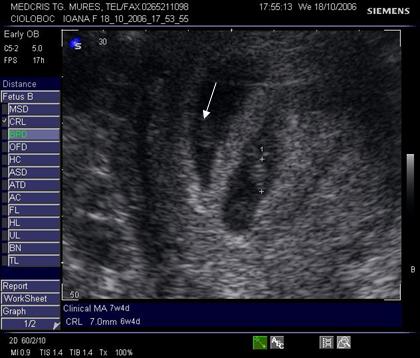

Fig nr 36 Sarcina gemelara biamniotica, 6 sapt, cu 2

saci amniotici si 2 embrioni (cu sageata )